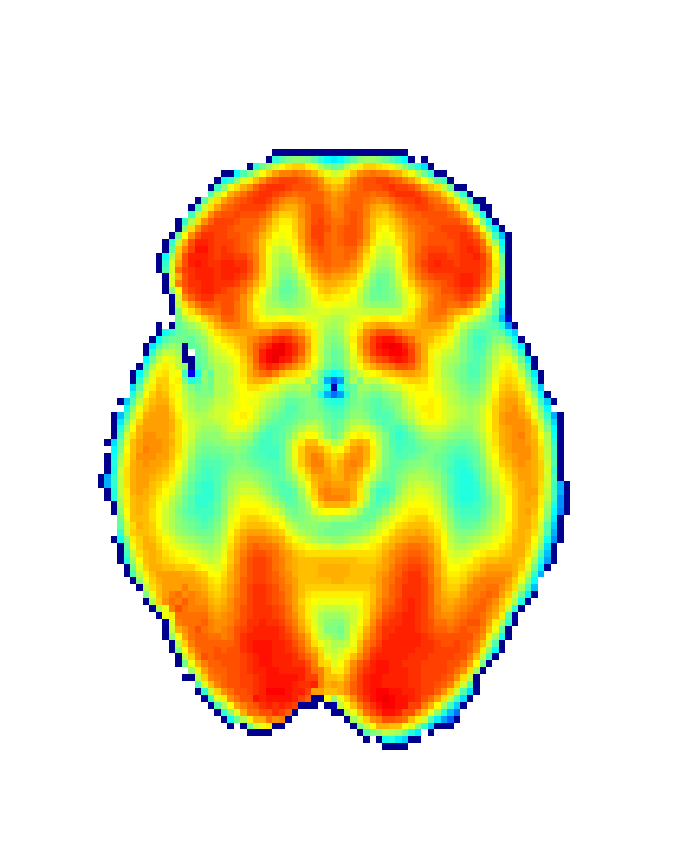

In order to obtain 18F-FDG PET data we drawn upon the Alzheimer’s Disease Neuroimaging Initiative (ADNI) [56], a platform that collects data from different research institutions focusing on AD diagnosis. We selected 18F-FDG PET and MRI data, together with demographic information (age and sex) for CN group (75 patients; 44 male; age: 75.56±4.96plus-or-minus75.564.9675.56\pm 4.96 years) and AD group (51 patients; 30 male; age: 74.03±7.25plus-or-minus74.037.2574.03\pm 7.25 years) summing 126 participants. Images were then realigned, unwrapped, co-registered with MRI data, spatially normalised, mean proportionally scaled, and masked following standard procedures deployed by SPM with the aim of guaranteeing voxel-to-voxel comparability between images (see Figure 2).

Refer to caption

(a) Raw image

(b) Normalized image

(c) Masked image

Figure 2: Stages of 18F-FDG PET processing. (a) Raw image obtained from ADNI, (b) image after anatomical standardization, (c) processed image after masking.